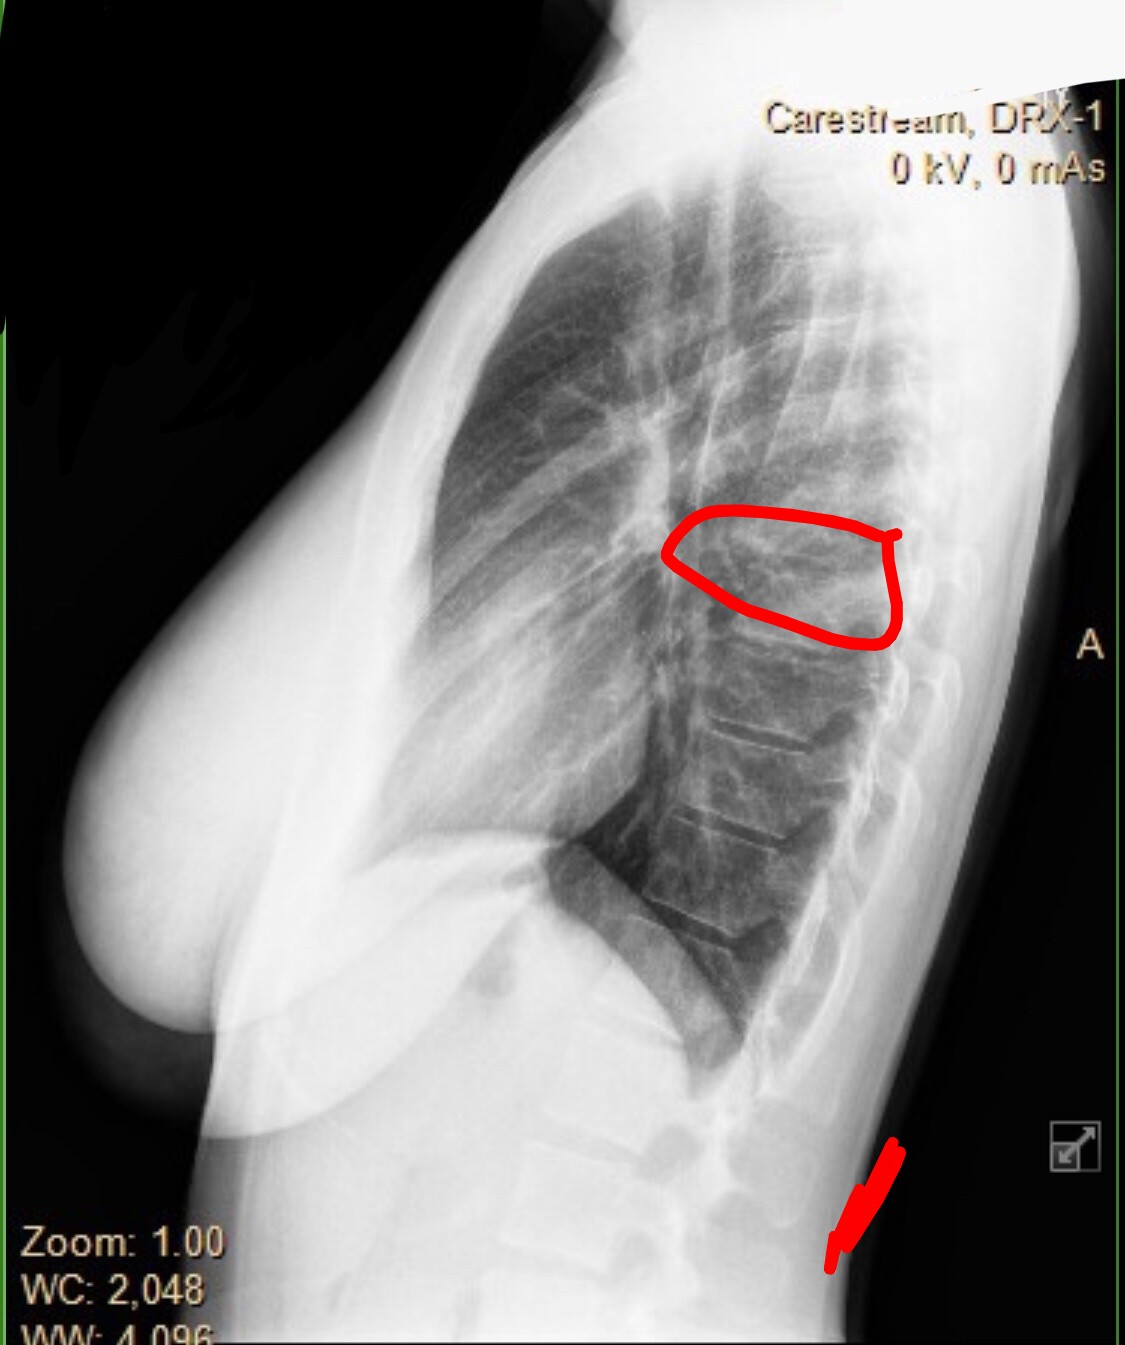

>warming up the snatch>get to 60kg >feel sharp pain in my upper back >power through it for the rest of the day>second day I can barely move>get xrayed and see thisIs it fucking over for me? I’m an Olympic hopeful for 2028

>>77050843Look at my c6. It’s not supposed to look like that

>>77050849that's your T6. your C6 is not present in this image. it could be spondylolisthesis, no one here knows doe

>>77050849C is cervical, and I see fuckall at your D6. nice tits tho. Also that's a very underexposed xray

Bro an x ray won't show a slipped disc or anything because it's soft tissue damageGet an MRI then get back to us Also nice tits

Is this what you're tripping over? Idk, it dosent look good, maybe a slipped disc.Your only hope now is get a real strong back to compensate.Didn't the doctor have any feedback for you, or did you just want to show us your tits, you slut? Not that i'm complaining.

>>77052406spondylolisthesis get a MRI